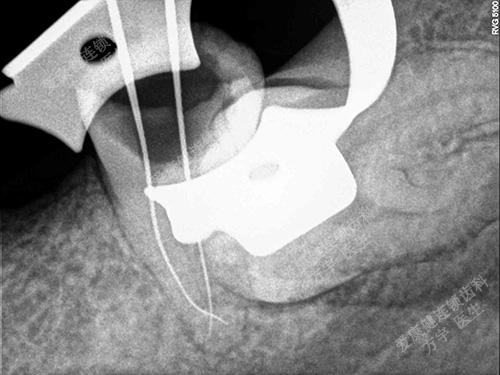

术前

术中